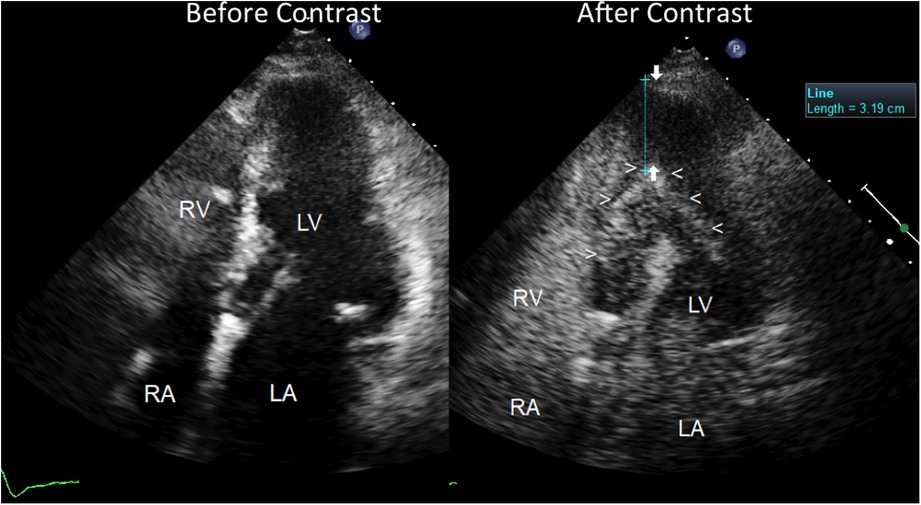

Figure 3

Severe apical left ventricular hypertrophy, as assessed by contrast enhanced transthoracic echocardiography. Four chamber view before (on the left) and after ultrasound contrast injection (on the right). Before contrast, the LV apical region does not show any clear delineation of the endocardial border but reveals a fairly homogeneous low backscatter echo-structure resembling a blood pool. No evident abnormality of the LV apical region can be noted but just poor quality imaging of the apical region with scarce delineation of the endocardium; the pace-maker leads can be noted in the right atrial cavity. On the contrary, after contrast injection (Sonoview® 1 cc in bolus) (on the right), a perfect delineation of the true apical endocardium is very clearly depicted as a hyper reflective line of backscatter (arrowheads). The severe hypertrophy of the LV apical wall can be noted and measured, as indicated by arrows (>3 cm thickness). The left atrium is dilated. The right atrial cavities are filled with contrast medium. LV = left ventricle; RV = right ventricle; RA = right atrium; LA = left atrium.

Owing to an uncertain picture of the LV apex function and morphology, since the endocardial border was not visible at that level, we decided to use contrast enhancement, using Sonoview® contrast medium, Bracco Diagnostics: each ml of the dispersion contains 8 μl of sulphur hexafluorane in the microbubbles, equivalent to 45 micrograms (8). The duration of enhancement after a bolus is longer than 3 min, so we injected 1 ml of bolus solution, allowing the duration of the enhancement to cover 3 min of scanning. The contrast very clearly depicted the endocardial border of the apex cavity as a hyper reflective line that delimited a restricted apex cavity, partially filled with contrast medium. The restricted LV apical cavity showed a typical “ace-of-spades"-like configuration, with severe apical hypertrophy (maximal thickness = 3.6 cm) (Figure 3) and hyper-normal ejection fraction (74%). Thus, a reliable diagnosis of apical HCM could be made.